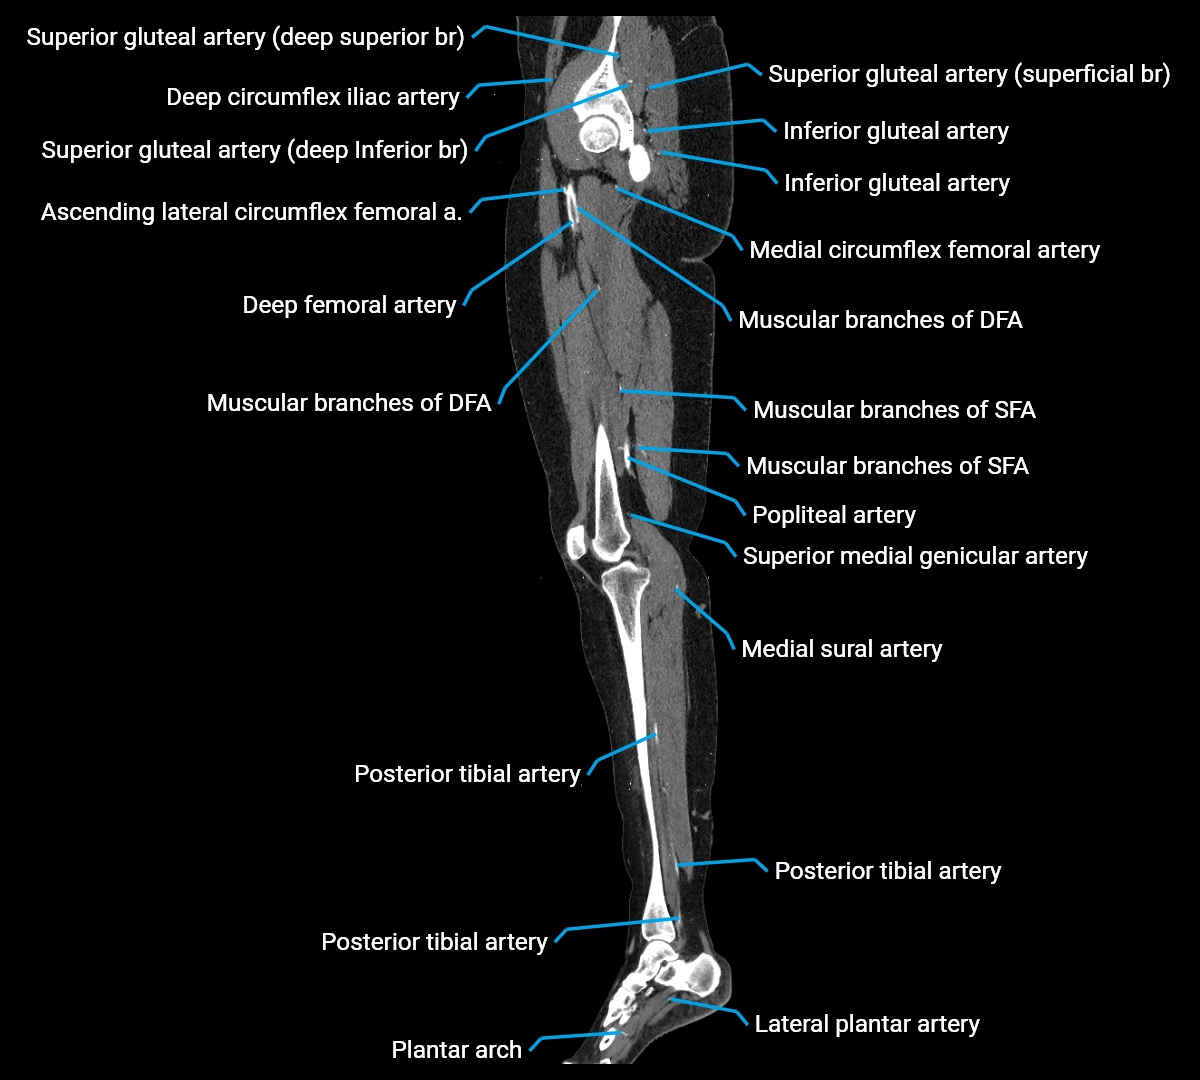

Contrast-enhanced CT (CTA):

• Gold standard for abdominal aortic imaging

• Provides excellent detail of lumen, wall, aneurysm, thrombus, and branch vessels

• Multiplanar and 3D reconstructions help in aneurysm measurement, stent graft planning, and dissection evaluation

• Detects acute rupture, traumatic injury, or occlusion with high sensitivity